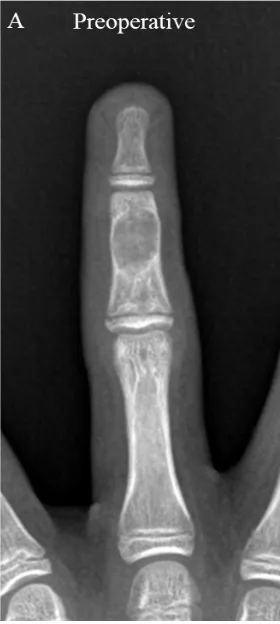

中指の中節骨に生じた内軟骨腫のX線写真.

引用元:Kang SJ. Differences in outcomes based on the degree to which bone defects are filled with cancellous allochip bone grafts in hand enchondroma patients. Cancers (Basel) 2024. 16.

1件目の手術は, 中指の中節骨に生じた内軟骨腫という軟骨性良性腫瘍の切除術でした.

骨にドリルで孔を開けた後, 腫瘍を鋭匙という器具で掻き出してから, 人工骨を詰めます.

当科では, 空洞に詰める人工骨にレボシス-Jという綿状の人工骨を使っています.

顆粒状の人工骨と違って, 小さな孔を開けた骨に詰め込みやすいのが特徴です.

予定通り, 30分弱で終了.